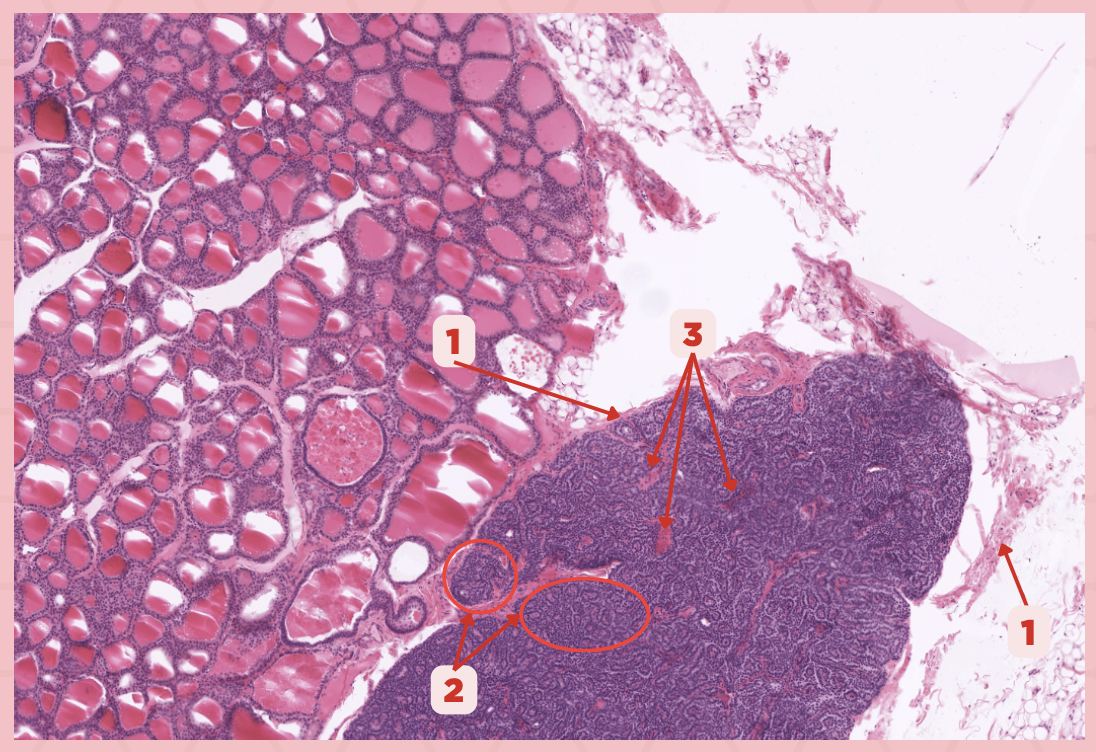

Parathyroid

Identify the specimen.

Chief Cells

Identify the specimen labeled as 1.

Oxyphil Cells

Identify the specimen labeled as 2.

Adipocytes

Identify the specimen labeled as 3.

Capillaries

Identify the specimen labeled as 4.

Newborns

Pointer #2 is hardly present in the parathyroid glands of _____.